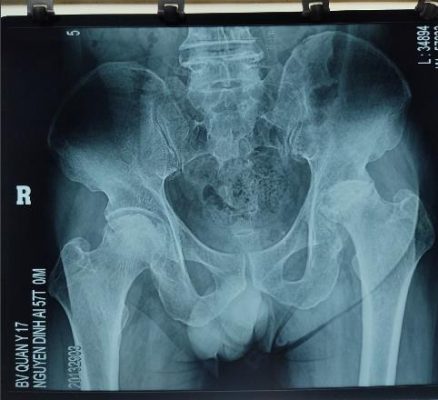

Hoại tử vô mạch chỏm xương đùi độ 4 Thay khớp háng toàn phần điều trị hoại tử vô mạch chỏm xương đùi

( Ficat)

- Bệnh lý khớp háng: hoại tử vô mạch chỏm xương đùi giai đoạn 3, 4 (Ficat); thoái hoá khớp háng , hư khớp háng do lao, sau nhiễm khuẩn khớp háng ổn định.